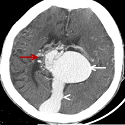

Anévrysme de la veine de Galien révélé à l’âge adulte

Badreeddine Alami, Mustapha Maaroufi

PAMJ. 2014; 19: 102. Published 29 September 2014